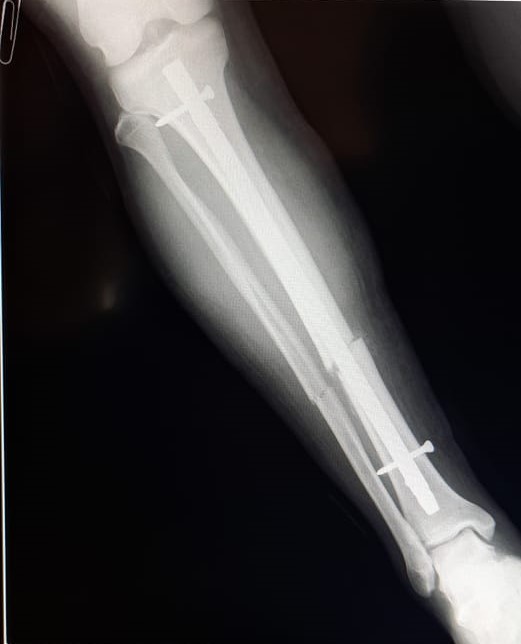

Se realizó una osteosíntesis endomedular de pierna derecha a un hombre de 35 años que no posee obra social. La prótesis fue solventada en su totalidad por el sistema público de salud. La cartera sanitaria destacó la realización de este tipo de cirugía en un hospital subzonal.

El procedimiento se llevó adelante teniendo en cuenta que el hombre se había fracturado la tibia y el peroné derecho.

El equipo quirúrgico que efectuó la osteosíntesis endomedular de pierna derecha, estuvo conformado por los médicos traumatólogos Enzo Fuentes, del Hospital Subzonal de El Maitén, y Javier Galván y Juan Ayestaran, del Hospital Zonal de Esquel; y el médico anestesiólogo Luis Miy, del Hospital de El Maitén.